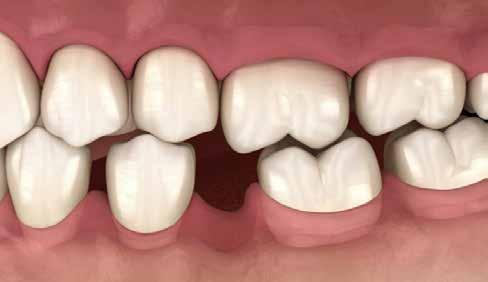

frontfogak esztétikailag is kellemetlen megjelenést biztosítanak, ugyanakkor mivel a frontfog stop nem elégséges, így az állkapocs előrecsúszását eredményezi, majd a fogak a nagymetszőkön támaszkodva további funkcionális problémát is okoznak. A fogérintkezés problémái az izomzatban is jelentkeznek, a kompenzációk szinte azonnal láthatók az arcon, később a test izmain, a testtartáson is. Különböző fogérintkezési problémák izomkompenzációs mintázata teljesen típusos megjelenésű, leolvasható a testtartásból, sőt az arcról is.